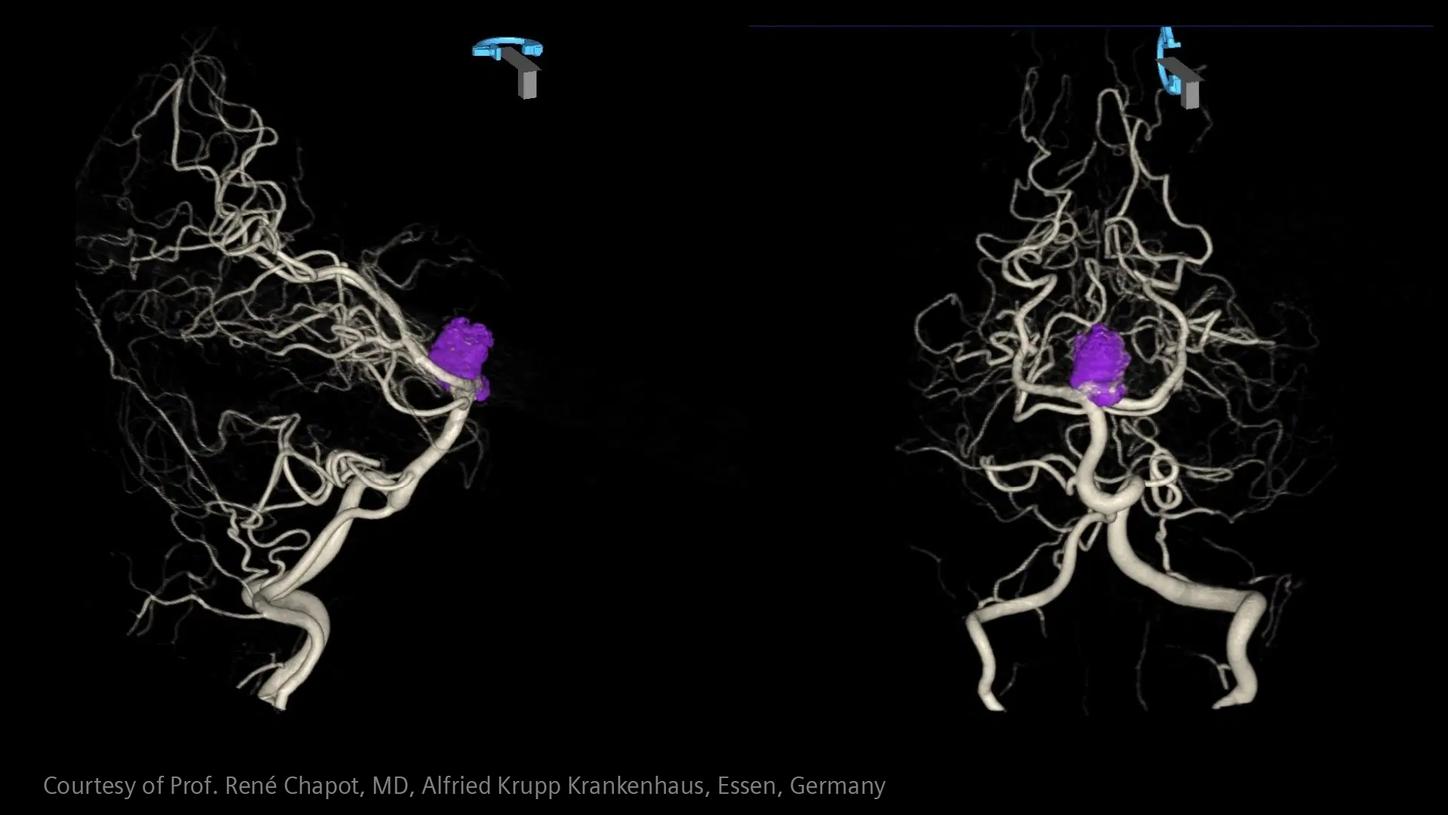

Critical insights in seconds:

How advanced imaging and AI transform stroke workflow

In stroke care, time is brain. Rapid and accurate imaging is crucial to assess the extent of brain injury and guide immediate treatment. Angiography, MRI, CT, ultrasound, and lab diagnostics are essential tools in identifying stroke type, location, and severity. Advances in imaging technology now allow for even faster acquisition, improved resolution, and enhanced visualization of brain tissue and blood vessels. Innovations such as perfusion imaging, real-time vascular mapping, and AI-assisted diagnostics are transforming stroke workflows and enabling precise, timely interventions.